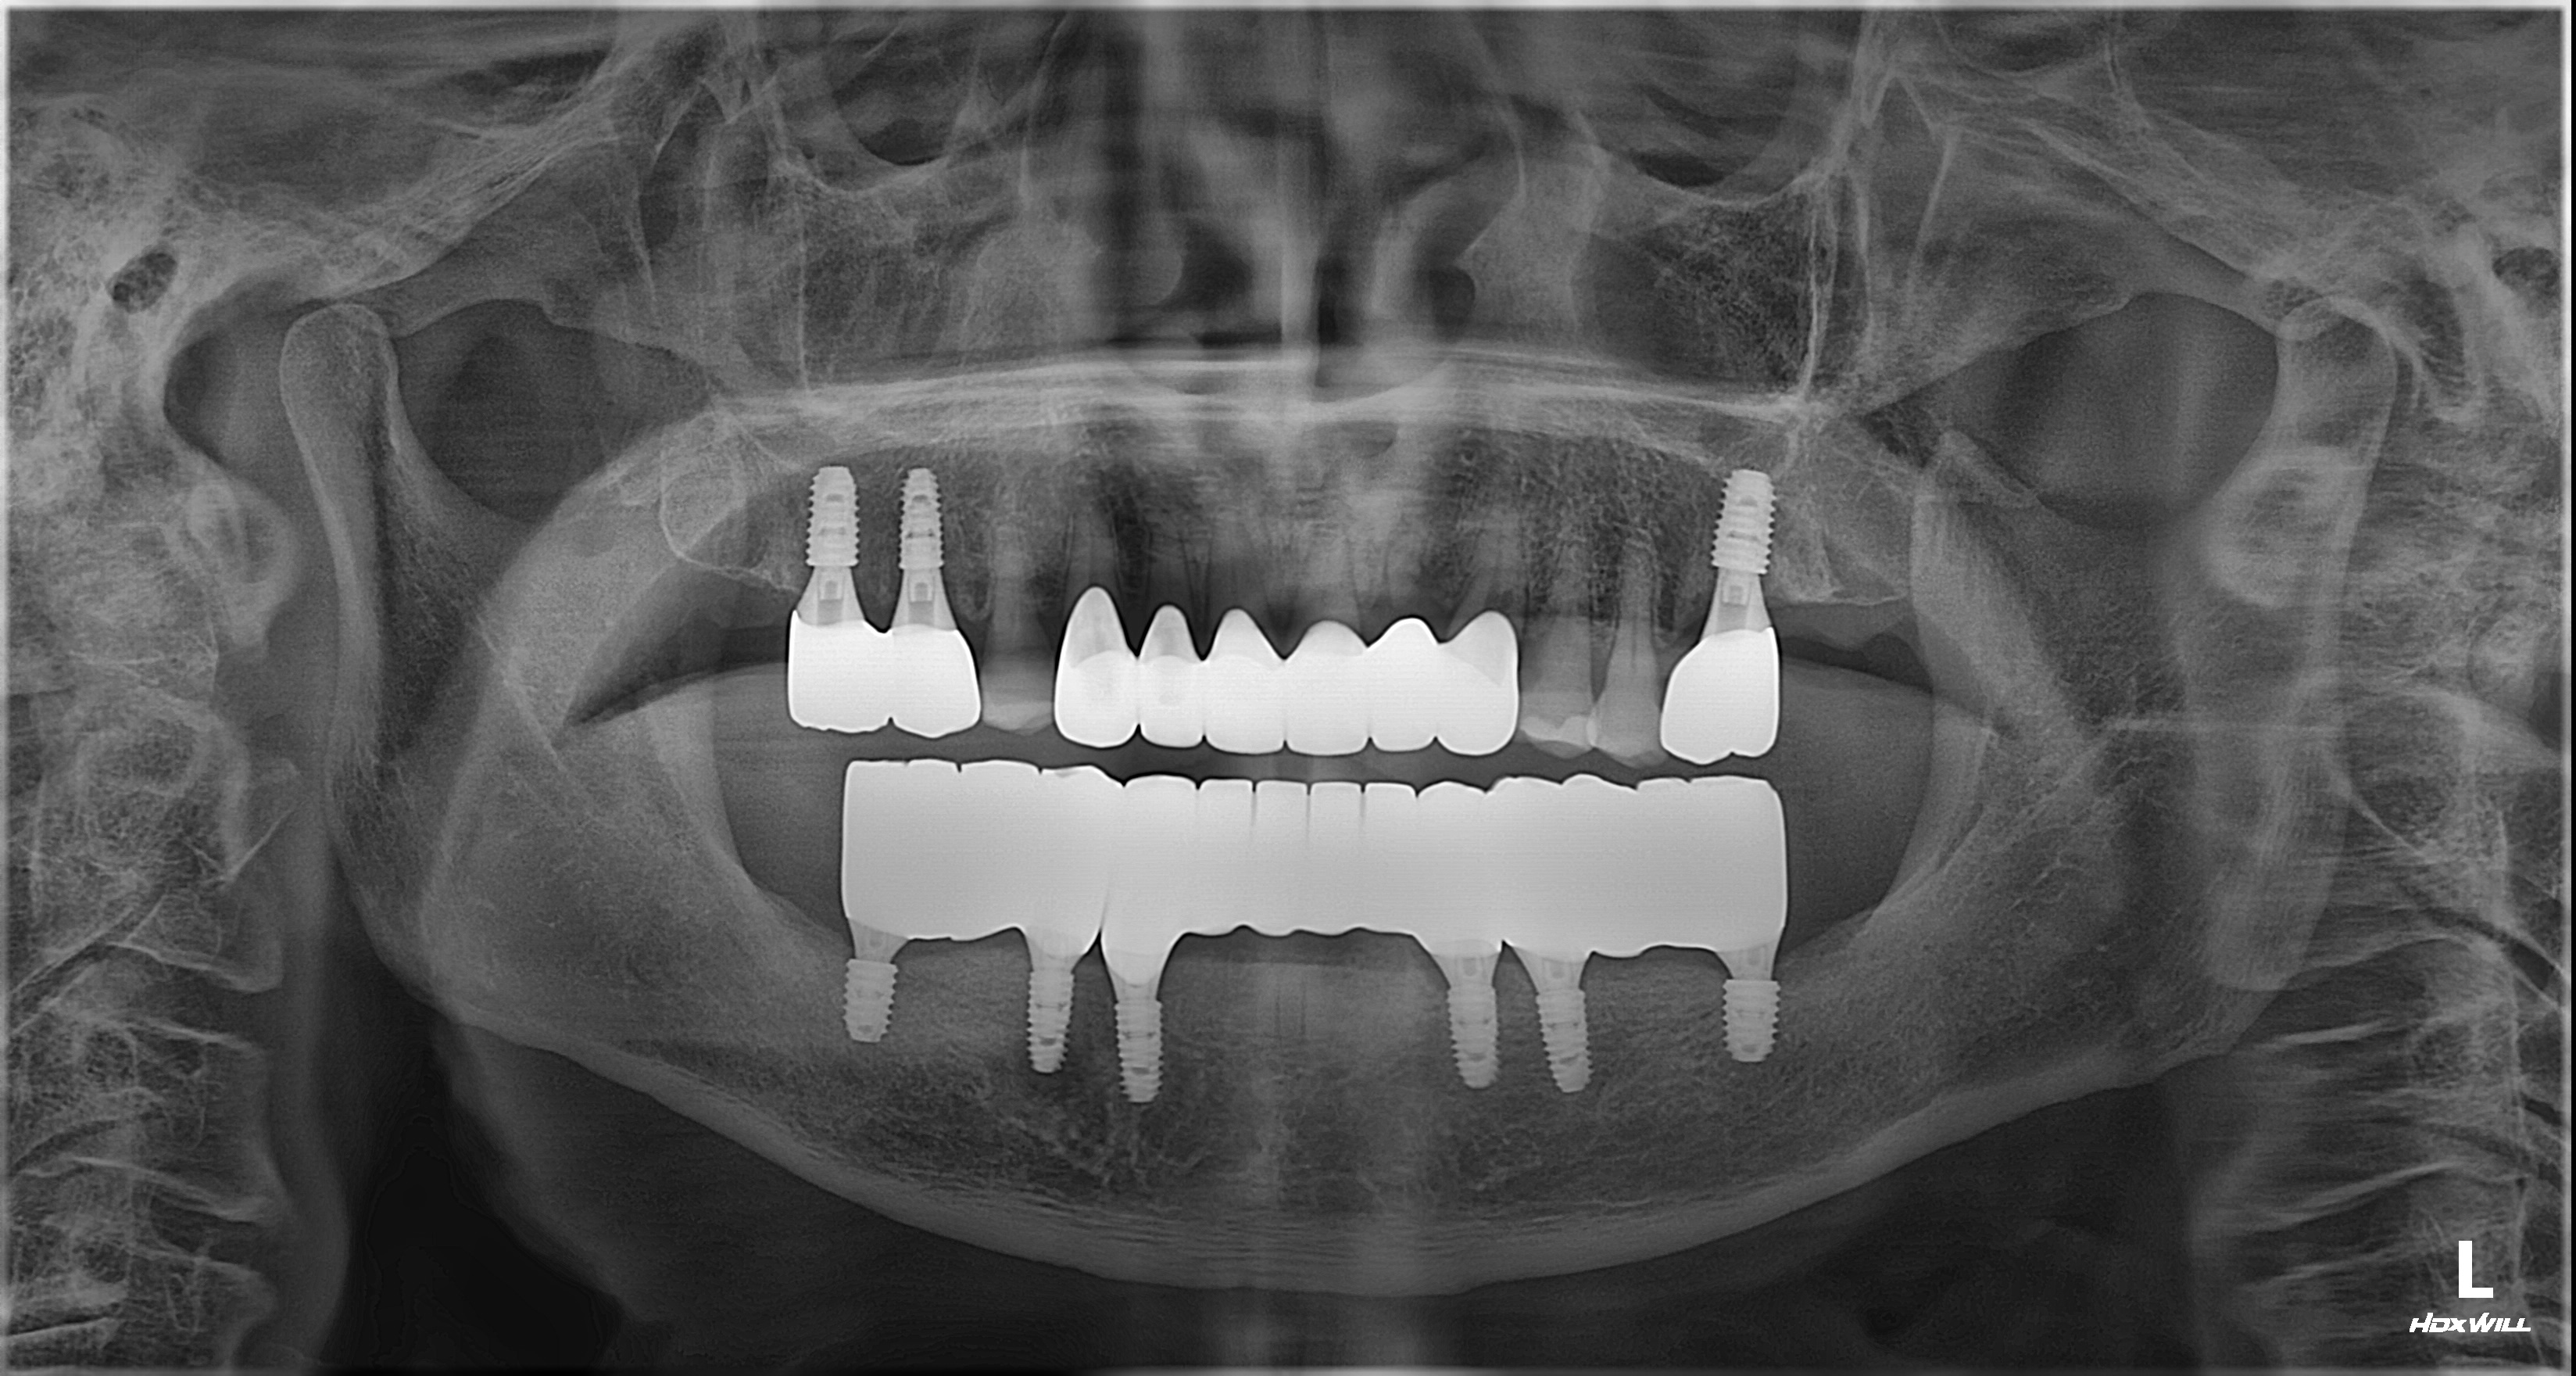

촬영일시: 2024.10.05.

촬영일시: 2025.03.29. [ 치료기간: 2024년 10월 05일 ~2025년 03월 29일 ] ※ 365서울앞선치과의원의 모든 컬럼은 각 진료과 의료진이 직접 작성합니다. 365서울앞선치과의원 임상 케이스 게시물은 환자분께 의학적으로 정확하고 상세한 정보를 드리기 위해 각 진료과 의료진이 직접 작성하며, 모든 증례 사진은 본원 의료진이 직접 시술한 증례를 촬영한 것으로, 의료법 제23조, 제56조에 의거하며 환자분의 동의를 얻어 포스팅에 사용하였습니다. 또한 해당 케이스는 본 환자분의 치료 결과이며, 환자 상태에 따라 치료의 결과는 달라질 수 있습니다. |